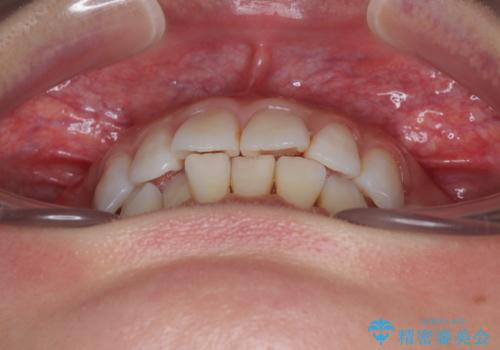

- 上下前歯の後戻りを気にして来院された患者様です。

インビザラインでの治療を希望されていて、デコボコの程度が中等度であり、安価なパッケージにて対応可能と判断されたため、インビザライン・モデレートを用いて矯正治療を行うこととしました。